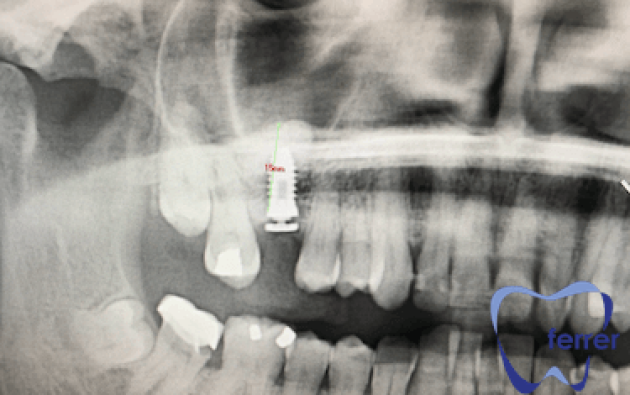

Tras colocar el injerto de hueso dental, habrá que vigilar muy bien el área y esperar unos meses para que se complete el proceso de osteointegración.

Durante este periodo de cicatrización, el hueso injertado se va integrando con el hueso natural del paciente, formando una estructura sólida que permitirá la colocación del implante con todas las garantías.

Mediante revisiones clínicas y nuevas pruebas de imagen, confirmamos que la regeneración ósea avanza correctamente antes de programar la colocación del implante. Así garantizamos un resultado predecible, seguro y duradero.